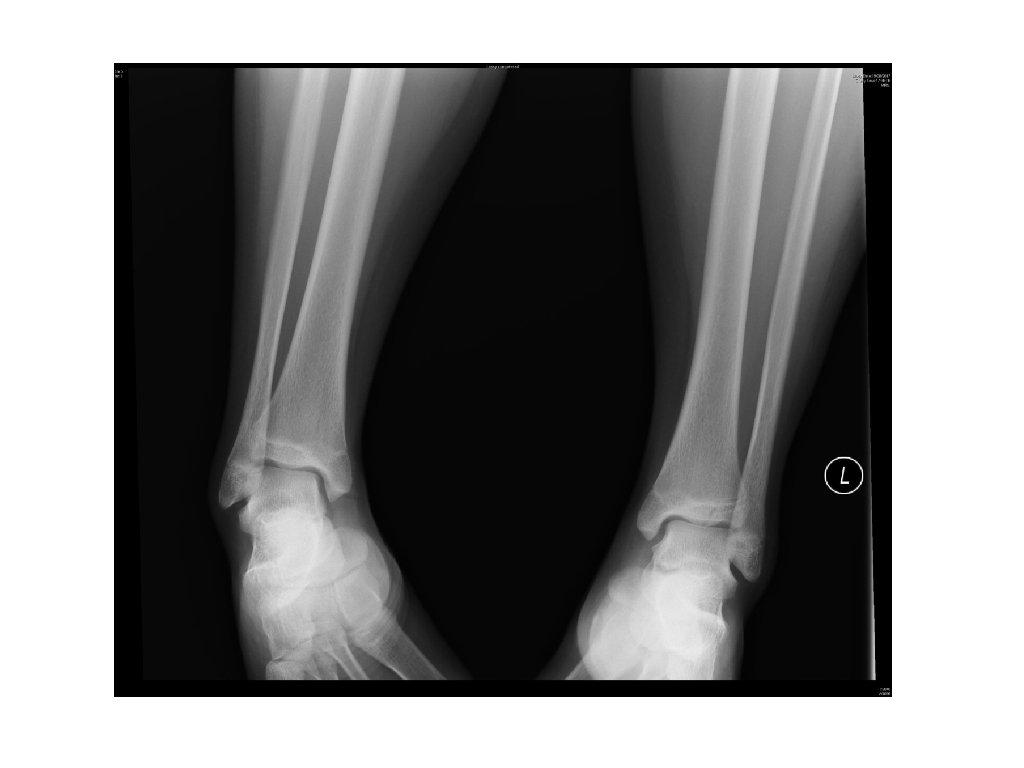

Case 5 • A 14 years old boy tripped and sprained left ankle at pool side. • He complained of pain and swelling in the ankle. Physical examination revealed local tenderness and swelling. He was unable to walk. • A X-ray was done.

Case 5 - Questions 1) What is the diagnosis? 2) What is the Salter-Harris type? 3) What is the mechanism of this injury? 4) What is the indication of operative management?